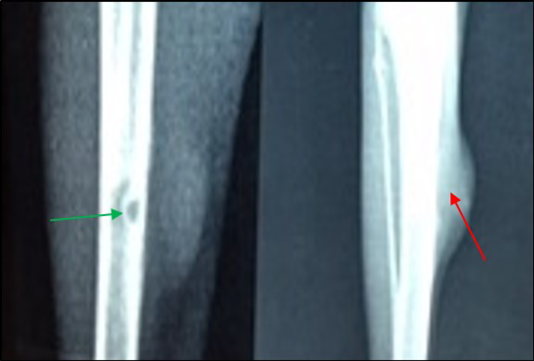

14 days post infection with MRSA, Area of bone lysis (Radiolucent spot) (→) surrounded by bone production (Radiopaque area) (→).Thickened cortex and severe periosteal reaction (→) (ML view)

A) 21 days post infection with MRSA shows Sever bone lysis (→), Thickened of cortex and sever periosteal reaction (→), Soft tissue suppuration (→) (ML view); B) Seqeustrum appeared (→) and abscesses (→) (AP view)